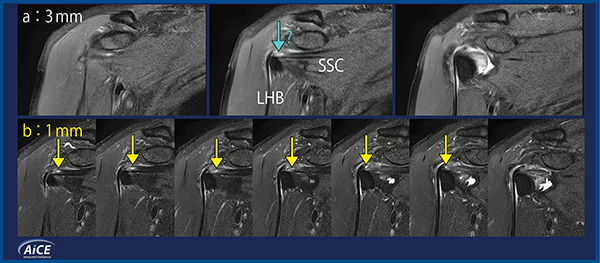

図1は,右肩甲下筋腱断裂症例の脂肪抑制プロトン密度強調画像(冠状断像)における,2D 3mm(a)と2D 1mm(b)の比較である。2D 3mm画像では,肩甲下筋腱(SSC)の最頭側に断裂があるように見えるが(a↓),1スライスのみでしか描出されておらず,パーシャルボリューム効果の影響の可能性もあり,確信が持てない。一方,2D 1mm画像では,複数スライスにわたって肩甲下筋腱の線維方向の断裂が確認できる(b↓)。上腕二頭筋長頭腱(LHB)の脱臼もなく,軽度高信号はマジックアングル効果によるものと推察される。MPR画像(図2)では,横断像(b)や矢状断像(c)でも肩甲下筋腱の断裂(↓)が明瞭に描出されており,上腕二頭筋長頭腱の脱臼を防ぐ上関節上腕靱帯(b↓)などの軟部組織も確認できた。2D 1mm画像の所見は関節鏡の所見とも一致していた。

図1 右肩甲下筋腱断裂症例における2D 3mmと2D 1mmの画像比較

(画像ご提供:京都桂病院整形外科・新井隆三先生)